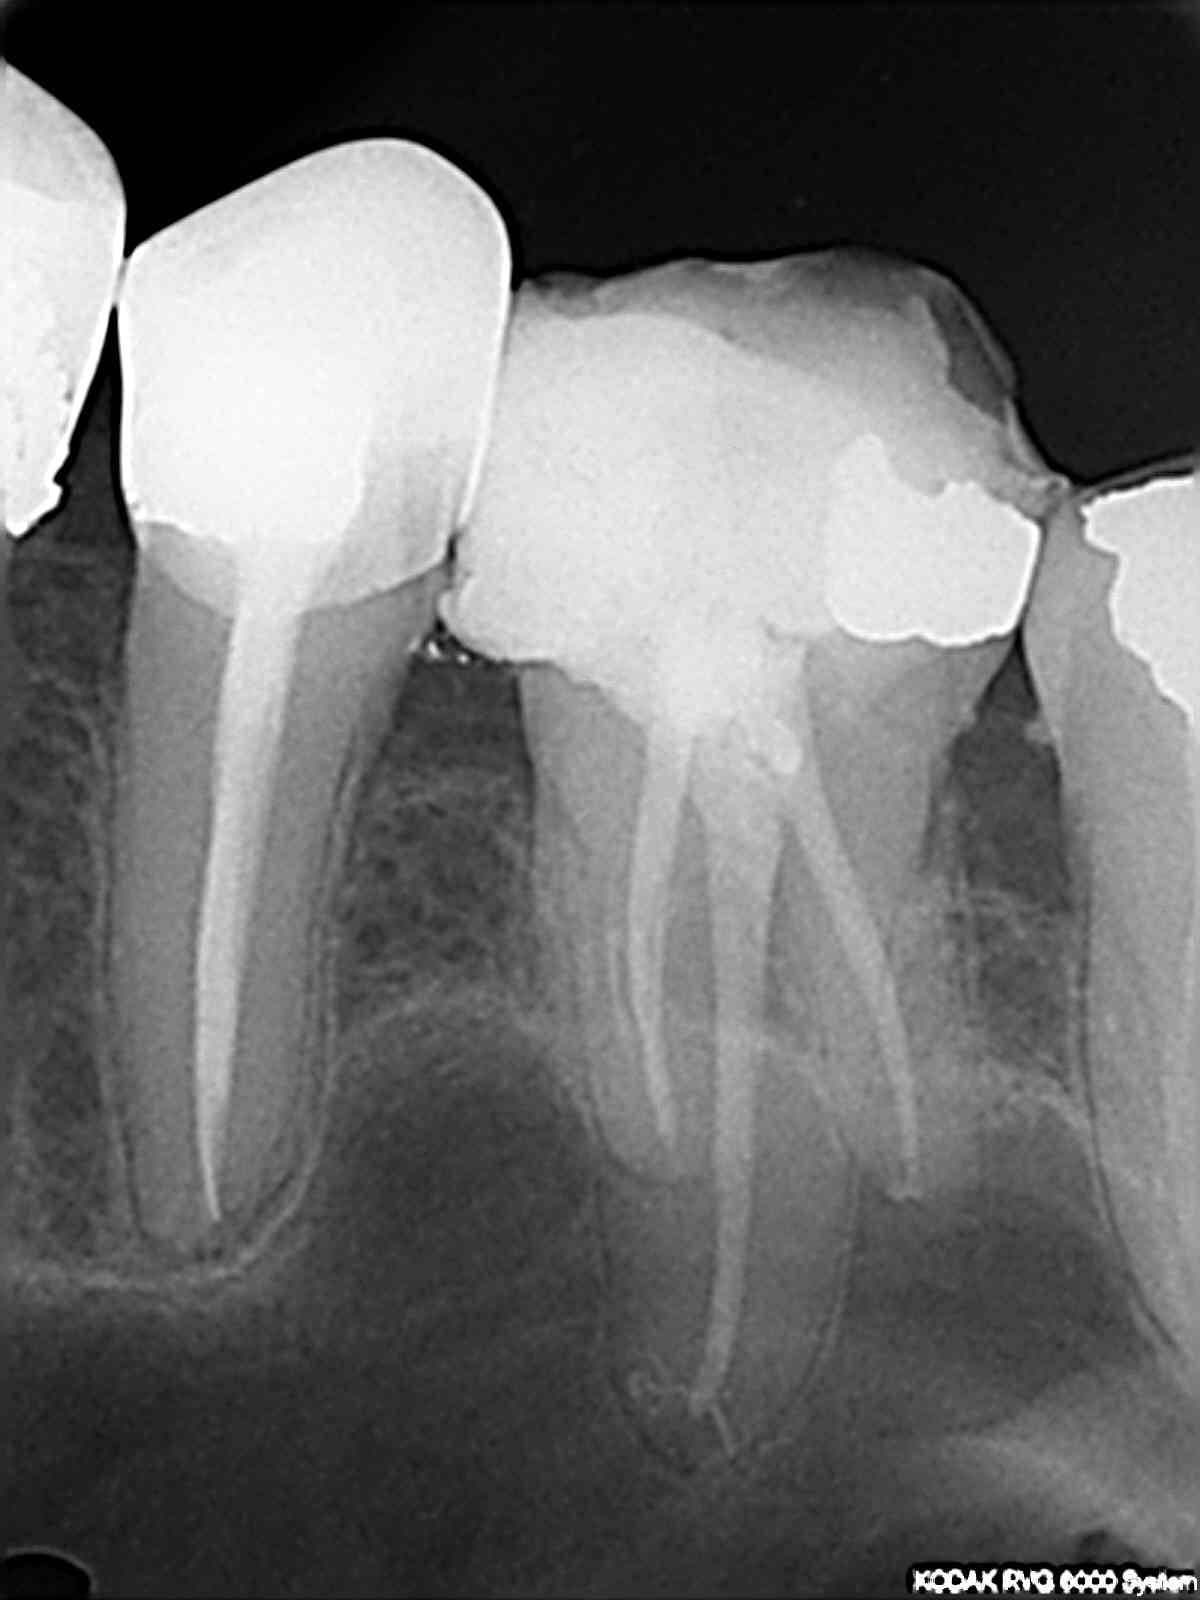

Sur la 14, c'est un Mc Spadden cassé dans la gutta: ça c'est assez fréquent mais pas très génant: instrument stérile noyé dans la gutta.